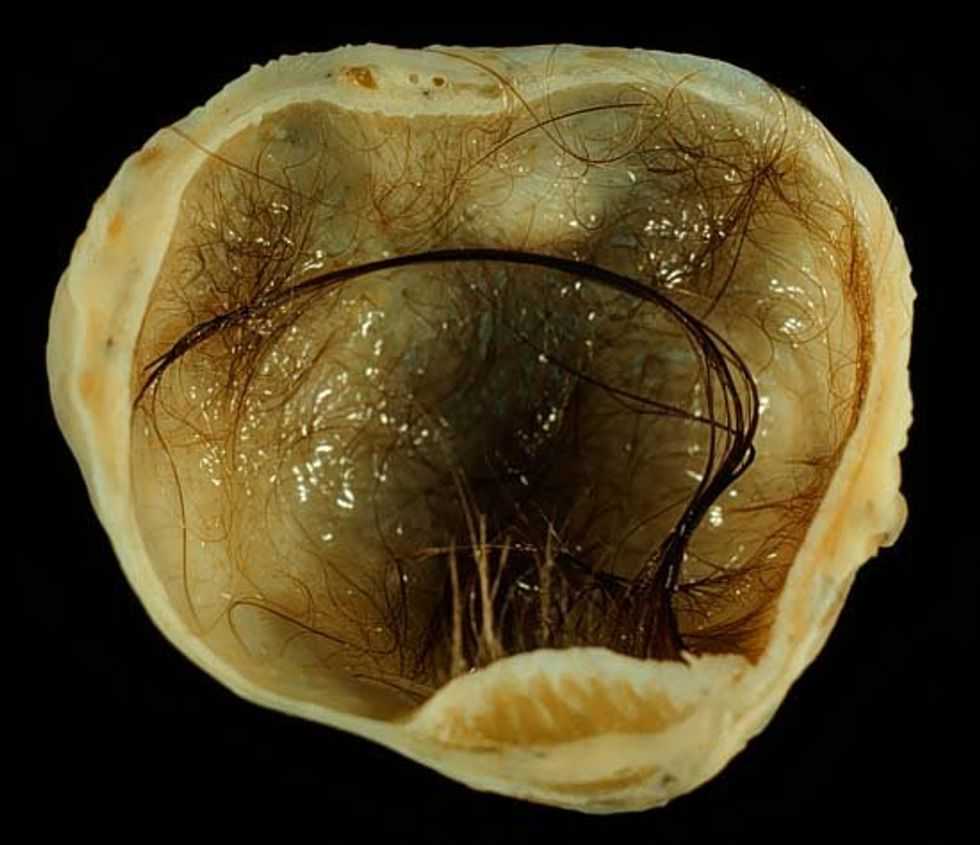

It was a teratoma—a unique kind of tumor that grows from germ cells (cells that eventually become sperm or, in Stuthers’ case, eggs). Because of their origin, teratomas frequently grow hair and even teeth, along with various kinds of tissue. The teratoma inside Stuthers’ ovary had all that, and more… The surgeons even thought Stuther’s teratoma may have had an eyeball! (Later testing ruled this out… close call!) Typically, they grow in women’s ovaries but men can get teratomas as well, usually showing up in the testicles.

Mostly, people just wanted to know if they could see a picture of the actual teratoma. Stuthers did eventually show a photo briefly in a follow up video, but luckily for us, we can get a better look at these things through a plethora of high-res online images.

Ready? If you’re squeamish, you might want to look away now.

(Sorry, one more photo incoming.)